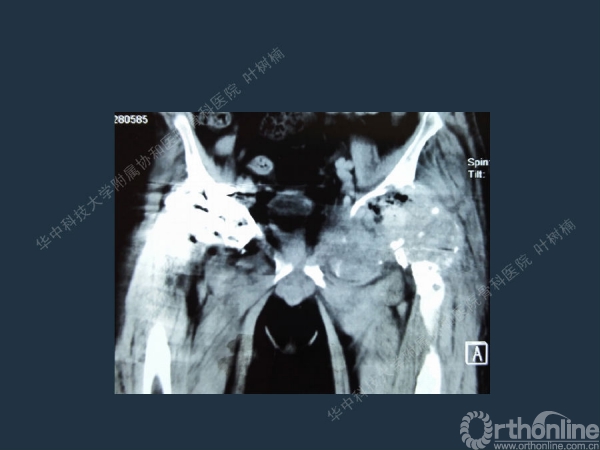

股骨侧翻修

髋臼缺损的处理